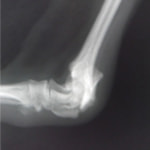

症例3:キルシュナーワイヤーのピンニングによる整復

ペルシャ猫 11ヶ月齢 雄

他院にて左大腿骨遠位の成長板骨折(salter-harrisⅠ型)が認められており、治療相談を目的として来院。当院にて、キルシュナーワイヤーを用いたピンニングにより骨折部位の整復を行いました。術後の経過は良好で、現在も経過観察中です。

術前レントゲン

術後レントゲン

機器

Arthrex社のターゲティングデバイスを用いてピンニングの位置を調整することで、確実な固定を行っています。当院ではこの手術器具以外にも、人の手術にも使用される様々な器具を導入し、手術精度を高め、また医療メーカーと新しい器具の開発、試作にも取り組んでおります。